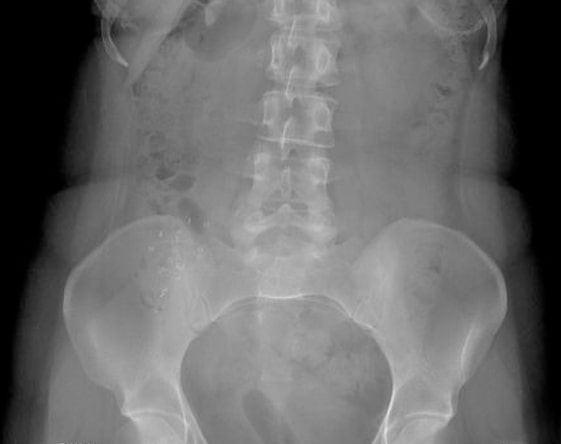

Colon Transit Study

Diagnosis of Constipation. A kind of diagnostic test that evaluates the function of the colon or ...